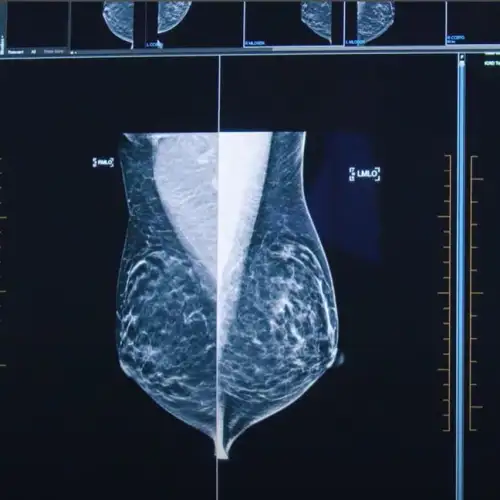

Our breast team is one of the most experienced in the UK, offering seamless access to advanced screening, imaging, and surgical services. Using the latest diagnostic technology, including 3D mammography and ultrasound, our consultants provide accurate results quickly and safely, followed by expert continuing care. We understand that breast concerns can be sensitive and sometimes worrying. That’s why we ensure every patient receives clear information, fast results, and compassionate, consultant-led support throughout their journey. Working closely with our women’s health specialists, we deliver fully coordinated care tailored to each individual’s needs, from early detection to complex surgical management.

TestWomen's HealthEnhanced Breast Screening (Mammogram)Our enhanced breast screening service enables the early detection of breast cancer in patients who do not have symptoms.

TestWomen's HealthBreast Triple AssessmentA breast triple assessment is the gold standard of testing for accurately detecting and diagnosing breast cancer and breast tissue abnormalities.

Fast, accurate diagnosis with breast triple assessment

Traditional breast investigations often require multiple appointments, leading to anxious waits for answers. If you have symptoms, our breast triple assessment provides a clear diagnosis in a single visit, combining expert examination, advanced imaging, and same-day biopsy when required. You’ll receive precise results and a personalised plan without delay — offering clarity, reassurance and confidence in your next steps.